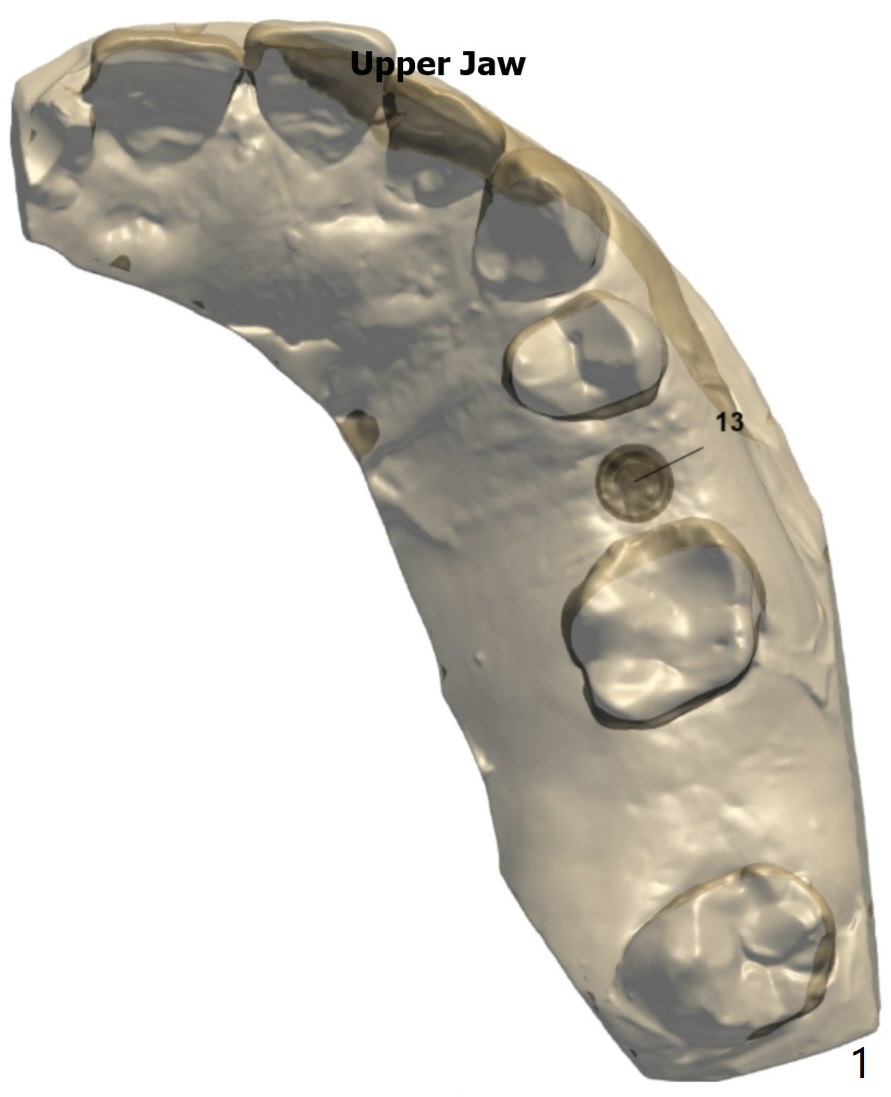

~ 6 months post socket preservation, bone density ~ 1000 units.

Xin Wei, DDS, PhD, MS 1st edition 03/02/2020, last revision 03/10/2020